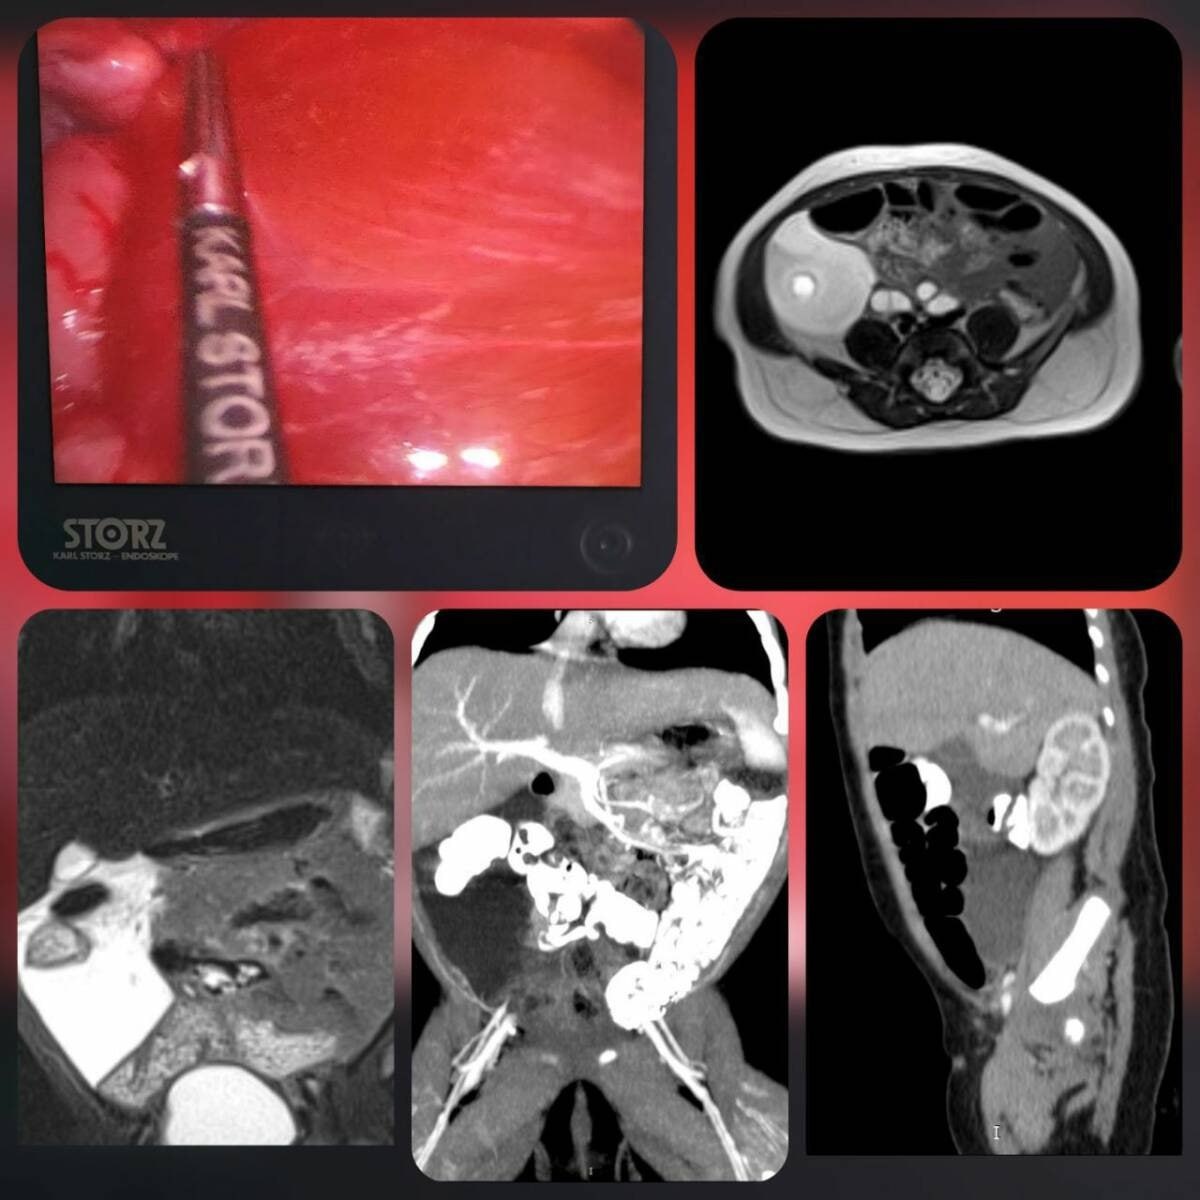

Π₯ΠΈΡ€ΡƒΡ€Π³ΠΈ Π²ΠΏΠ΅Ρ€Π²Ρ‹Π΅ ΠΏΡ€ΠΈΠΌΠ΅Π½ΠΈΠ»ΠΈ ΠΈΠ½Π½ΠΎΠ²Π°Ρ†ΠΈΠΎΠ½Π½ΡƒΡŽ ΠΌΠ΅Ρ‚ΠΎΠ΄ΠΈΠΊΡƒ лСчСния лимфатичСской ΠΌΠ°Π»ΡŒΡ„ΠΎΡ€ΠΌΠ°Ρ†ΠΈΠΈ Ρƒ ΠΌΠ»Π°Π΄Π΅Π½Ρ†Π°.

Π Π΅Π±Π΅Π½ΠΊΠ° срочно госпитализировали Π² ΠΎΡ‚Π΄Π΅Π»Π΅Π½ΠΈΠ΅ Ρ…ΠΈΡ€ΡƒΡ€Π³ΠΈΠΈ Π΄Π΅Ρ‚Π΅ΠΉ Ρ€Π°Π½Π½Π΅Π³ΠΎ возраста с ΠΊΡ€ΡƒΠΏΠ½Ρ‹ΠΌ кистозным ΠΎΠ±Ρ€Π°Π·ΠΎΠ²Π°Π½ΠΈΠ΅ΠΌ Π² Π±Ρ€ΡŽΡˆΠ½ΠΎΠΉ полости, ΠΊΠΎΡ‚ΠΎΡ€ΠΎΠ΅ выявили Π½Π° Π£Π—Π˜.

ПослС комплСксного обслСдования спСциалисты ΠΏΠΎΠ΄Ρ‚Π²Π΅Ρ€Π΄ΠΈΠ»ΠΈ Ρ€Π΅Π΄ΠΊΡƒΡŽ аномалию развития лимфатичСских сосудов Π² Π±Ρ€Ρ‹ΠΆΠ΅ΠΉΠΊΠ΅ толстой кишки.

Β«ΠžΠΏΠΈΡΠ°Π½Π½Ρ‹ΠΉ случай являСтся ΠΊΡ€Π°ΠΉΠ½Π΅ Ρ€Π΅Π΄ΠΊΠΈΠΌ. Π’Π°ΠΊΠΈΠ΅ случаи Π²ΡΡ‚Ρ€Π΅Ρ‡Π°ΡŽΡ‚ΡΡ ΠΏΡ€ΠΈΠΌΠ΅Ρ€Π½ΠΎ Π² 4 Π½Π° 100 000 госпитализаций. Π›Π΅Ρ‡Π΅Π½ΠΈΠ΅ ΠΊΡ€Π°ΠΉΠ½Π΅ слоТно ΠΈΠ·-Π·Π° высокого риска ослоТнСний: воспалСния, ΠΏΠ΅Ρ€Ρ„ΠΎΡ€Π°Ρ†ΠΈΠΈ, компрСссии сосСдних ΠΎΡ€Π³Π°Π½ΠΎΠ² ΠΈ лимфоистСчСния», – объяснили Π² прСсс-слуТбС Π”Π ΠšΠ‘.

Малоинвазивная опСрация ΠΏΡ€ΠΎΡˆΠ»Π° ΡƒΡΠΏΠ΅ΡˆΠ½ΠΎ, Π²Ρ€Π°Ρ‡ΠΈ сохранили сосуды ΠΊΠΈΡˆΠ΅Ρ‡Π½ΠΈΠΊΠ° ΠΈ ΠΏΡ€Π΅Π΄ΠΎΡ‚Π²Ρ€Π°Ρ‚ΠΈΠ»ΠΈ риск ослоТнСний.

ПослС лСчСния Ρ€Π΅Π±Π΅Π½ΠΎΠΊ Π±Ρ‹Π» выписан Π΄ΠΎΠΌΠΎΠΉ Π±Π΅Π· послСдствий.